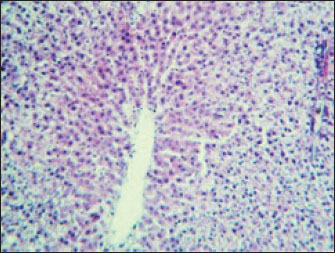

The histopathological results in the TCE group showed that the treatment with TCE for 90 days ( 110 LD50daily) resulted in the infiltration of inflammatory cells, mainly lymphocytes, in portal area with mild fibrosis, hyperplasia of the bile duct (Fig. 3) showed congested central vein, proliferation of Kupffer cells, apoptotic cells and, with dilated sinusoids, while the (Fig. 4) showed severe fatty changes of hepatocytes in the form of cytoplasmic lipid droplets (microvascular steatosis) with proliferation of Kupffer cells. (Fig. 5) showed degenerative changes with necrosis of hepatocytes with proliferation also (Fig. 6). Histopathological section of the liver (group + with oil) showing mild degenerative changes of hepatocytes. In Fig. 7, the histopathological section of the liver (c +group/90 days) showing mild degenerative changes of hepatocytes with few inflammatory cells infiltration (Fig. 8). Finally, in Fig. 9, histological section of the liver (control group) with normal structure.

Fig. 6. Histopathological section of the liver (TCE group/90 days) showing degenerative changes with necrosis of hepatocytes and proliferation of Kupffer cells ( H&E stain 400X).